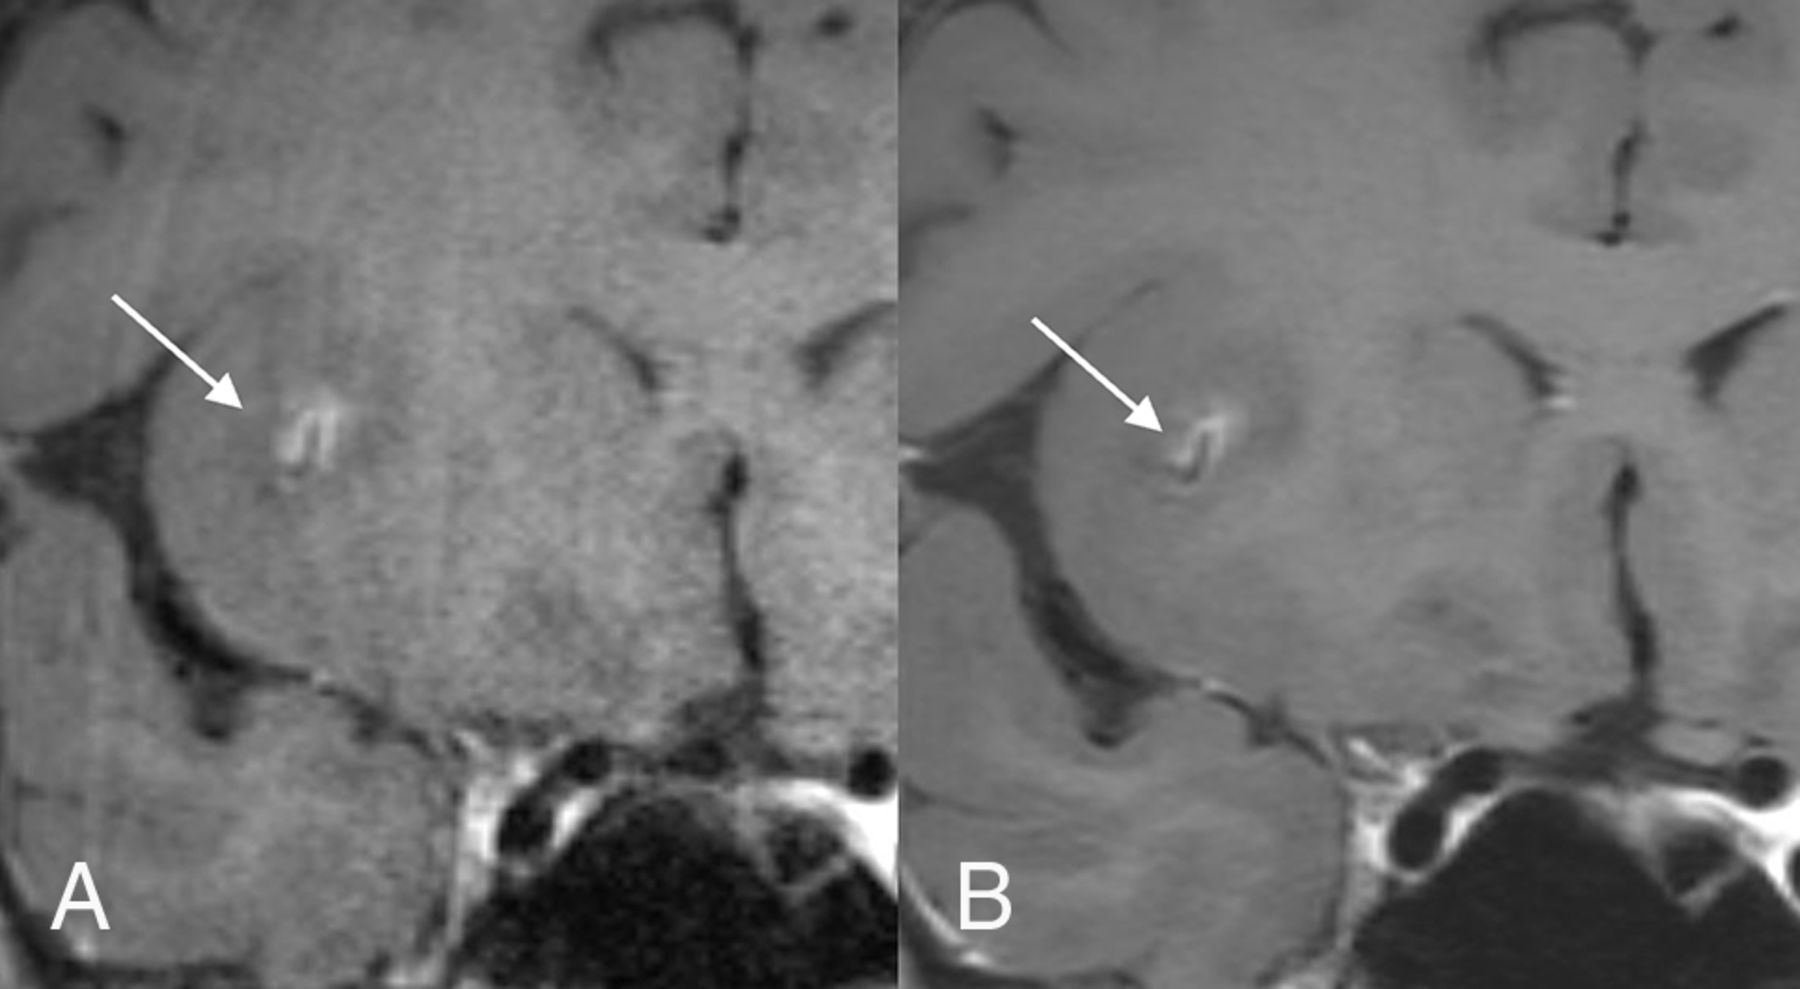

The mean vessel wall and lumen visualization scores for the noncontrast images in healthy volunteers (n = 10) are presented in Tables 2 and 3, respectively. The DLBIR images showed overall statistically significant improvement in vessel wall (10/11) and lumen (11/11) depiction in nearly all evaluated segments (Fig 1). For the basilar artery wall visualization, the DLBIR images were rated better in quality though the difference was not statistically significant.

Coronal MPR images of the clinical (A) and DLBIR (B) sequence showing better visualization of the ICA terminus bilaterally, along with reduced background image noise (B).

Similar trends were also noted for the postcontrast sequences in patients (n = 5), in which DLBIR images were consistently rated better for wall and lumen visualization (Tables 2 and 3), with the image-quality differences being statistically significant in most segments (vessel wall [7/11]; lumen [7/11]). DLBIR images were consistently rated as having the lowest image noise (60/60 [15 subjects × 4 readers]) and more uniform CSF signal (60/60) by all readers, and as having higher image sharpness (45/60) by most readers. The depiction of various intracranial findings was also consistently noted to be similar or better on the DLBIR images (Figs 2–5). Flow artifacts in the distal vessels were noted to be overall similar but better seen on the DLBIR images, given the reduced image noise and improved image sharpness.